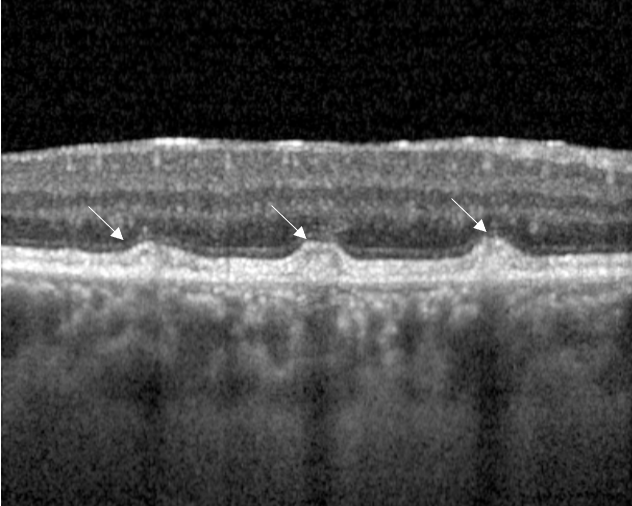

OCT coupe sur les « flecks » (flèches)